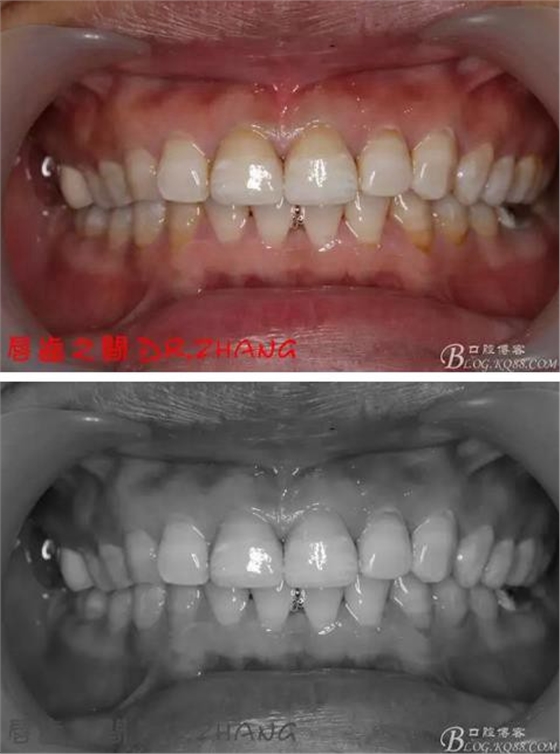

復(fù)診:臨時牙良好 患者自訴無不適癥狀 去除臨時修復(fù)體 排齦 清理牙面 試戴全瓷修復(fù)體后粘結(jié) 常規(guī)醫(yī)囑 不適隨診

總結(jié):沒有術(shù)前照片 預(yù)備牙體過長 顏色還是有差距